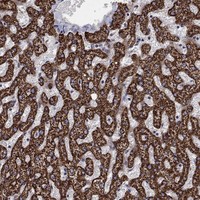

Immunohistochemical staining of human liver shows strong cytoplasmic positivity in hepatocytes.